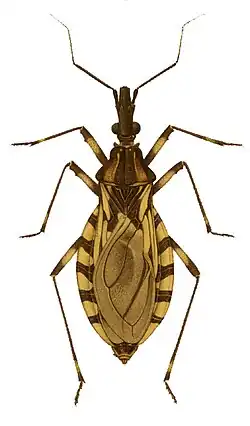

| Imagem microscópica do Trypanosoma cruzi, o agente infeccioso da Doença de Chagas | |

Doença de Chagas ou Tripanossomíase americana é uma doença tropical parasitária causada pelo protozoário Trypanosoma cruzi e transmitida principalmente por insetos da subfamília Triatominae. Os sintomas mudam ao longo do curso da infecção. Na fase inicial, eles podem não estar presentes ou podem ser: febre, gânglios linfáticos aumentados, dor de cabeça e inchaço no local da mordida. Após 8-12 semanas, os indivíduos entram na fase crônica da doença e em 60-70% nunca desenvolvem outros sintomas. Os 30 a 40% restantes apresentam sintomas adicionais de 10 a 30 anos após a infecção inicial. Isto inclui o alargamento dos ventrículos do coração em 20 a 30% levando a insuficiência cardíaca. A dilatação do esôfago ou o alargamento do cólon também podem ocorrer em 10% das pessoas.

T. cruzi é transmitido para humanos e outros mamíferos principalmente pela via vetorial, geralmente através do contagio com as fezes de insetos hematófagos da subfamília Triatominae, popularmente denominados de "barbeiros" (p. ex.: Triatoma infestans). A doença pode também ser transmitida através de transfusão de sangue, transplante de órgãos, ingestão de alimentos contaminados com o parasita e da mãe para o feto. O diagnóstico precoce da doença é feito pela detecção do parasita no sangue, utilizando um microscópio. A forma crônica é diagnosticada pela presença de anticorpos para T. cruzi no sangue.

Nas áreas endêmicas, o principal mecanismo de transmissão é o vetorial, ou seja, através de um inseto vetor da subfamília Triatominae,[3] principalmente dos gêneros Triatoma, Rhodnius e Panstrongylus.[4] O inseto infecta-se com Trypanosoma cruzi ao alimentar-se de sangue de animais ou humanos contaminados. De hábitos noturnos, ele esconde-se durante o dia em fendas nas paredes e telhados, e emerge à noite, quando os habitantes estão dormindo. Por causa da tendência de picar a face das pessoas, o inseto é popularmente conhecido como "barbeiro" ou "chupão". Após a picada e a ingestão de sangue, ele defeca próximo ao local. O prurido intenso no local da picada ajuda as formas infectantes de T. cruzi (denominadas de tripomastigotas), nas fezes, a penetrarem na ferida da picadura, mas elas também podem penetrar por mucosas intactas, como a conjuntival.[3]